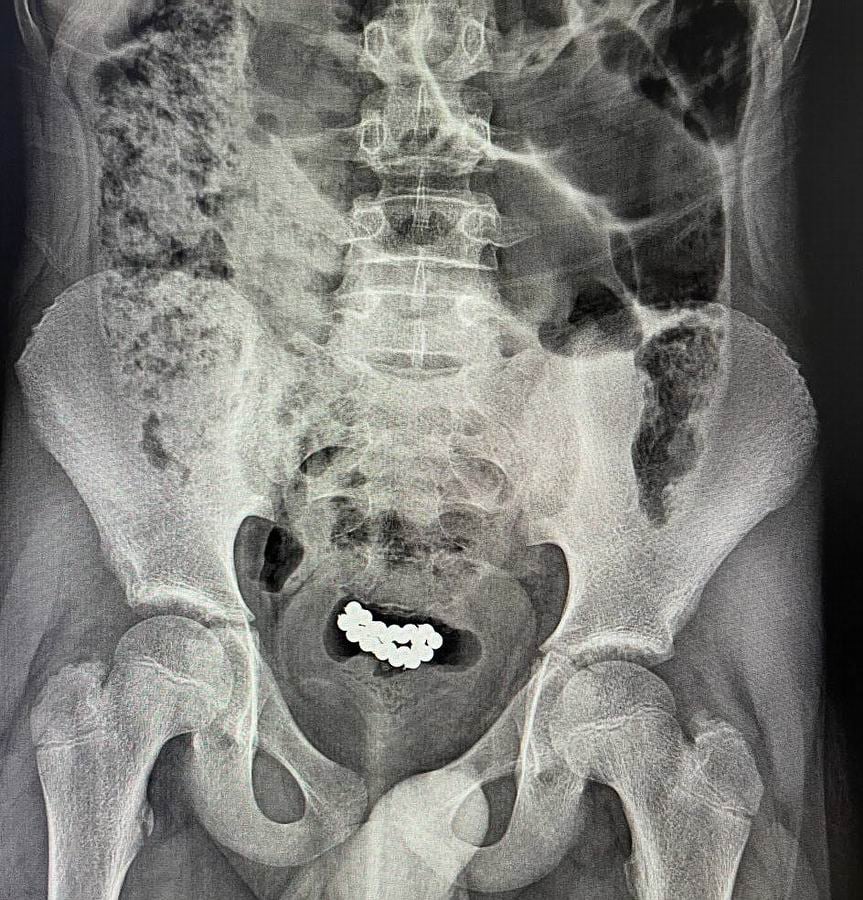

У нашому закладі успішно було прооперовано два ідентичних випадки евакуації магнітних кульок з сечового міхура хлопчиків у віці 10-15 років. В обох випадках була виконана цистотомія міні-лапаротомним доступом з подальшим вилученням 62 і 24 магнітних кульок,

На фото лікарські знімки, на яких видно, чим загрожує необережне поводження з іграшками.